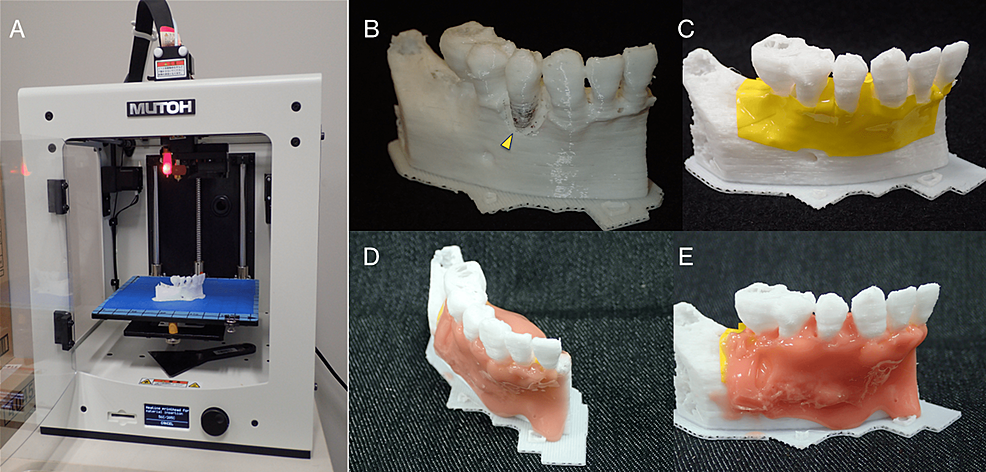

3D models for surgical training

The polygonal mesh models were created from Digital Imaging and Communications in Medicine (DICOM) images in STL format data using the medical image-processing software package Volume Extractor 3.0 (i-Plants Systems, Iwate, Japan) [6]. These data were based on the preoperative CBCT images. First, slicing software was used to generate control data of the 3D printer (G-code data). Three-dimensional anatomical osseous models of the teeth and jawbone were then fabricated using the desktop fused deposition modeling (FDM) 3D printer Value3DMagiX MF-800 (MUTOH Industries Ltd., Tokyo, Japan) (Figure 7A). The 3D printing parameters were as follows: filament used, 1.75-mm; polylactic acid resin (PLA) (Pxmalion, eTranslab Inc., New York, USA); lamination pitch, 0.2 mm; infill density, 33%; printing speed, 40 mm/sec; heated nozzle temperature, 210℃; without support structure or raft. To apply soft tissue to the teeth and jawbone in the 3D models fabricated with the 3D printer, the colored vinyl tape was pressed in to imitate the periosteum and then a silicone rubber-based impression material (Multisil-Mask Soft, Bredent GmbH & Co. KG, Senden, Germany) was applied manually to simulate the gum (Figure 7B–7E).

Although the slicing software (Cura customized for MUTOH, MUTOH Industries Ltd., Tokyo, Japan) calculated that the fabrication time for a 3D model would be about 2 h, the 3D printer used allowed the fabrication of five 3D models at a time, so altogether it took around 8 h. The actual cost of one teeth and jawbone 3D model for periodontal surgical training fabricated with the filament used (24 USD/1000 grams) was approximately 0.6 USD, including the cost of a few grams of silicone rubber-based impression material for the gum.

The surgical training shown in Figure 8 represents our newly proposed method for such, not a pre-packaged training course for resident dentists. Open-ended responses were obtained from the four resident dentists and two instructors who participated in this surgical training. Resident dentists’ feedback and comments are shown in Table 1.

By using this 3D model, we could see and touch the condition of the defect to be treated and thus know the amount of FGF-2 to use before the application. The main advantage of the FDM 3D printing system is its economic efficiency [20]. The availability of low-cost 3D models should increase the number of training opportunities. The key point here is that the 3D models that are fabricated are not those of typical cases, like those reflected in ready-made training models. Rather, they are custom-made and so faithfully replicate the specific conditions encountered in each patient.

However, because it is a low-end/personal desktop FDM 3D printer, it is not suitable for mass fabrication of 3D models in a short time. It is difficult to fabricate enough 3D models for surgical training when many trainees are to be taught on the same occasion. Moreover, there are also problems related to the materials to be used. Usually, only monochromatic and relatively hard materials such as PLA resin can be used presently, making it difficult to fabricate 3D models that reproduce soft tissues such as gum. It is hoped that softer materials will be available in the future that can reproduce soft tissues.